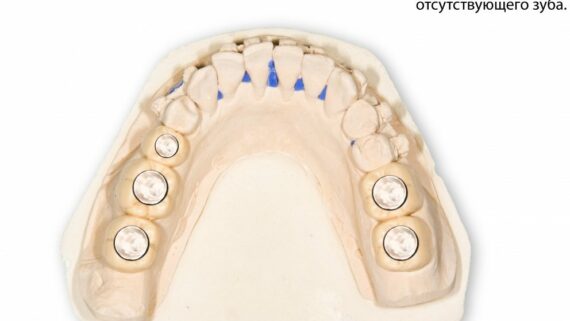

Остеопластические операции: факторы успеха. Часть II.